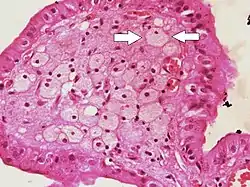

Foam cells (one indicated by arrows) visible in the finger-like projections into the gallbladder lumen in a case of cholesterolosis | |